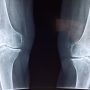

Dokter Reumatologi: Wanita Lebih Berisiko Terkena Osteoporosis

JAKARTA – Dokter spesialis penyakit dalam sekaligus konsultan reumatologi dari Fakultas Kedokteran Universitas Indonesia (FKUI) dr. Faisal Parlindungan, Sp.PD-KR, mengatakan,...